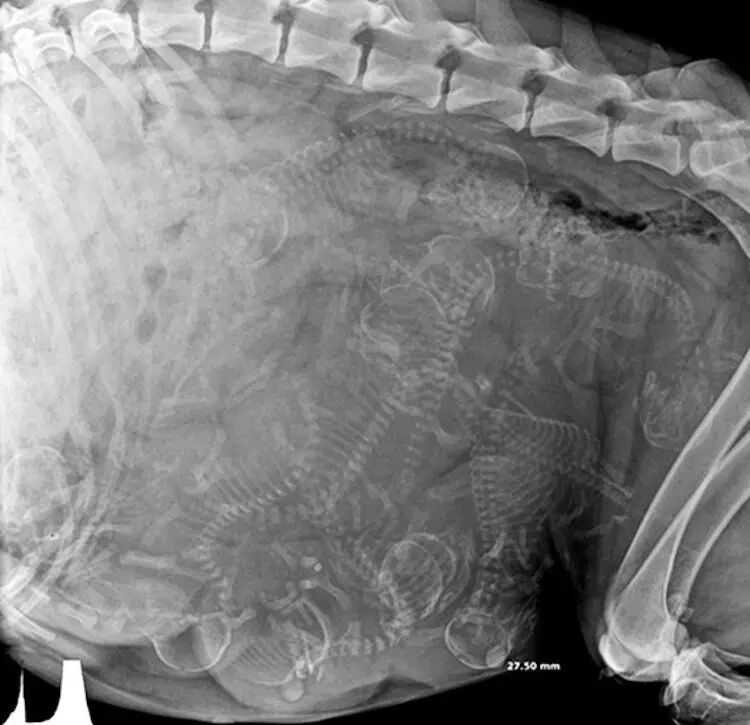

怀孕的狗。同样也是大概 45 天就能通过 X 光确认肚中的小狗。